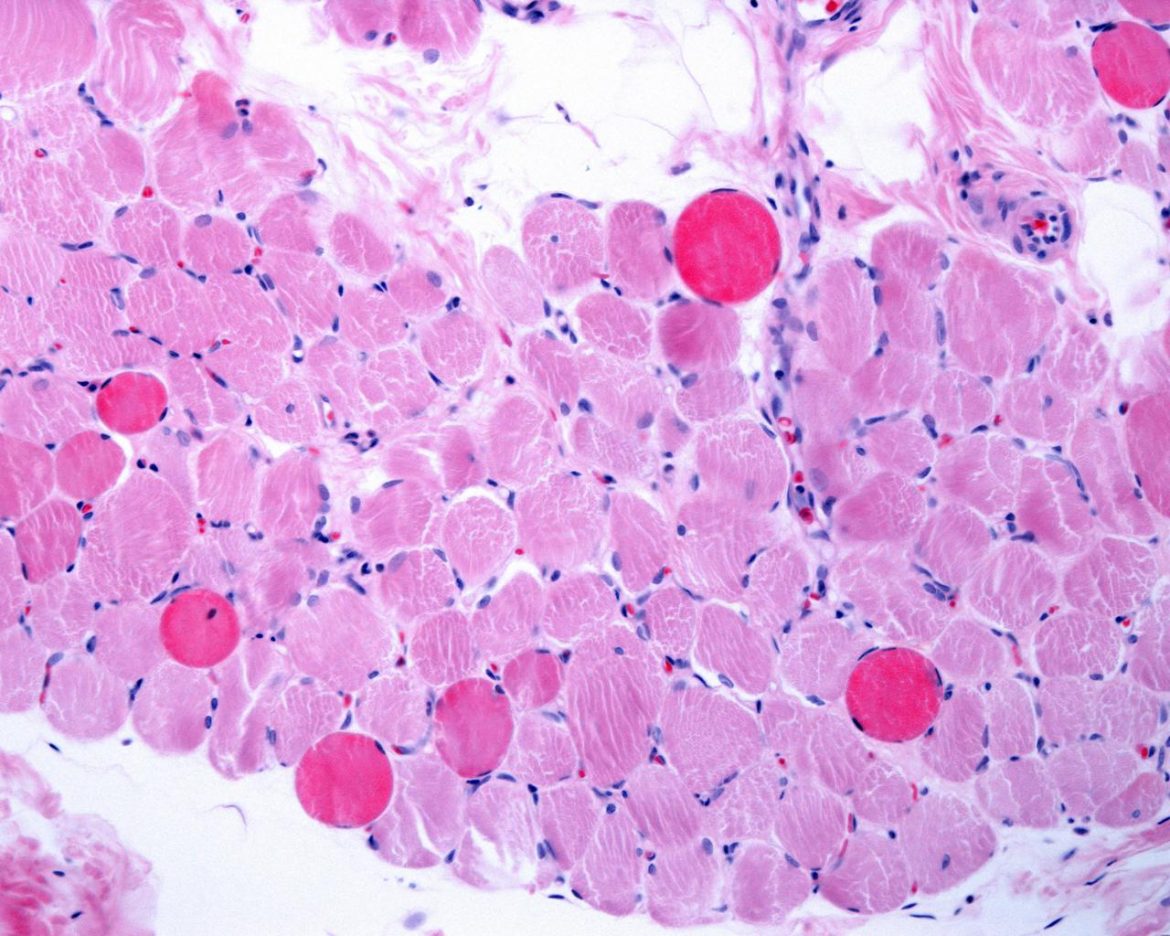

Roma, 3 mar. (Adnkronos Salute) – Al via la realizzazione di una piattaforma dedicata alla distrofia muscolare di Duchenne. L’iniziativa è promossa da Fondazione Telethon e “permetterà di organizzare in modo sistematico e coerente con gli standard più avanzati i dati di storia naturale raccolti in oltre 15 anni di studi clinici condotti in Italia. Una volta a regime la banca dati metterà a disposizione dei ricercatori i dati di centinaia di pazienti e al contempo porrà le basi per raccoglierne in futuro di nuovi secondo criteri e standard omogenei”. Lo comunica Telethon in una nota. Lo sviluppo della piattaforma – spiega la Fondazione – comporterà diverse attività di implementazione, tra cui: un’infrastruttura informatica per ospitare i dati; una scheda elettronica di raccolta dei dati (eCrf); documenti standardizzati come il consenso informato, materiali per la formazione, il dizionario dei dati; la codifica e la condivisione dei dati in linea con il regolamento generale sulla protezione dei dati (Gdpr); un’App interattiva per minimizzare gli errori nell’inserimento e nella gestione dei dati; altre attività supplementari per il mantenimento della piattaforma. Il progetto sarà realizzato grazie al supporto di alcune tra le più importanti aziende farmaceutiche ad oggi impegnate nello sviluppo di terapie per questa grave malattia neuromuscolare, per la quale nonostante gli sforzi non esiste ancora una cura risolutiva: Dyne Therapeutics Inc., Italfarmaco Spa, NS Pharma Inc., Roche Spa (il cui contributo sarà interamente dedicato allo sviluppo dell’infrastruttura informatica), Santhera Pharmaceuticals (Switzerland) Ltd, Sarepta International Holdings GmbH, Solid Biosciences Inc, elenca Telethon. “Siamo molto orgogliosi di annunciare questo progetto, che conferma come Fondazione Telethon sia in grado di fare da catalizzatore, forte della sua esperienza e reputazione – ha dichiarato il direttore generale Ilaria Villa – Di fronte alla necessità di disporre di dati più accurati e in linea con gli standard attuali, le aziende si sono affidate a noi per costruire uno strumento che in futuro sarà a disposizione di tutti e che auspichiamo possa accelerare la messa a punto di nuovi farmaci”.Il coordinamento della piattaforma sarà affidato a Eugenio Mercuri, direttore dell’Unità operativa di Neuropsichiatria infantile del Policlinico universitario A. Gemelli Irccs di Roma – Università Cattolica del Sacro Cuore, riconosciuto come uno dei massimi esperti del settore a livello internazionale. I principali centri clinici che nel corso degli anni hanno preso parte a studi che hanno coinvolto pazienti con la distrofia di Duchenne, finanziati da Fondazione Telethon grazie al bando congiunto con l’Unione italiana lotta alla distrofia muscolare (Uildm), metteranno a disposizione i dati raccolti e contribuiranno a popolare la piattaforma.